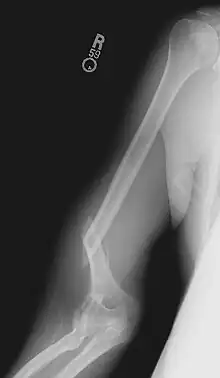

Blessures

Un bras de fer exerce un couple et une torsion importante sur l'os de la partie supérieure du bras, l'humérus, à un niveau rarement atteint dans d'autres activités physiques[14]. Les os de la plupart des humains ne sont pas habitués à de telles contraintes, et des blessures peuvent survenir très facilement. Le trait de fracture passe généralement au niveau d'une ligne située à mi-chemin entre l'épaule et le coude, ou un peu en dessous.

La tendance naturelle d'un pratiquant de bras de fer inexpérimenté est de pousser la main, le poignet et l'épaule dans la même direction de façon coordonnée, contre la force appliquée par l'adversaire. Toutefois, en tournant l'épaule de cette façon, on ne fait qu'ajouter de la pression à la torsion déjà appliquée à l'humérus par l'adversaire. US Arm Sports prévient du danger de « laisser votre épaule en avant de votre main ». Il est préférable de pivoter l'épaule et le bras, afin de ne jamais laisser la main en arrière de l'épaule.